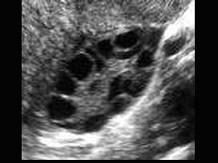

女性,月经过少,不孕就诊,超声图像可提示?(?)A.多囊卵巢B.卵泡发育不良C.卵巢巧克力囊肿D.正常卵巢E.以上都不是

问题 女性,月经过少,不孕就诊,超声图像可提示?(?)

选项 A.多囊卵巢 B.卵泡发育不良 C.卵巢巧克力囊肿 D.正常卵巢 E.以上都不是

答案 A